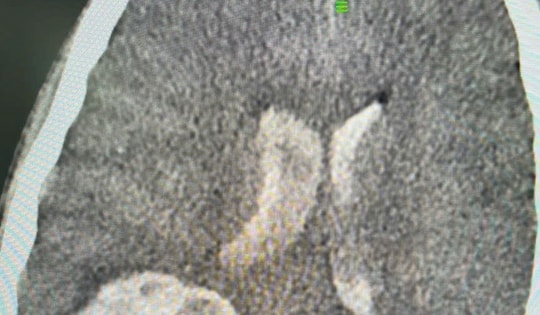

xuất huyết não

Cập nhập tin tức xuất huyết não

Bé trai 12 tuổi đột ngột đau đầu rồi rơi vào hôn mê sâu do xuất huyết não, tính mạng nguy kịch. Chạy đua với thời gian, các bác sĩ Bệnh viện Đa khoa Vinmec Times City đã kích hoạt quy trình cấp cứu tối khẩn, phẫu thuật ngay trong đêm để giành lại sự sống cho bệnh nhi.

Đi tàu lượn siêu tốc, người đàn ông trung niên bị xuất huyết não

Sau 20 ngày điều trị tích cực, bệnh nhân 87 tuổi bị xuất huyết não, hôn mê sâu đã hồi phục, cai được máy thở, sức khỏe dần ổn định trở lại.

Từ ca bệnh 13 tuổi bị xuất huyết não: Bác sĩ chỉ cách nhận biết nguy cơ từ sớm

Dị dạng mạch máu não thường không có triệu chứng rõ ràng, nhưng bệnh có thể gây ra hậu quả nghiêm trọng như đột quỵ, liệt nửa người, thậm chí tử vong.

Mở sọ não cứu sống bệnh nhân bị xuất huyết não nguy kịch

Khoa Ngoại Thần kinh Bệnh viện Đa khoa tỉnh Ninh Thuận vừa phẫu thuật thành công ca mở sọ, cứu sống nam bệnh nhân bị xuất huyết não do biến chứng tăng huyết áp.